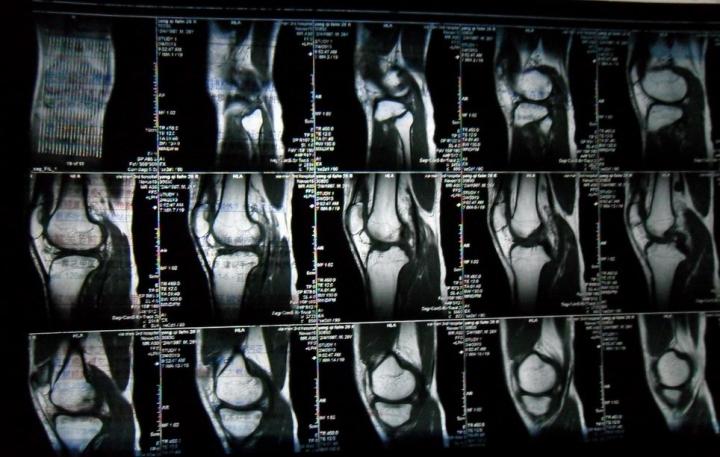

(图)半月板损伤核磁共振检查片子

目前身体的软组织病变诊断,主要途径就是拍核磁共振。在确定了是半月板损伤后,我的主治医生向我引出了一个重要的概念——半月板损伤根据损伤程度不同分为三级,一、二级说明伤势相对较轻,首选保守治疗。因为一二级损伤手术对半月板的干预,大于它本身受到的伤害;一旦半月板损伤被评估为三级,医生的建议是尽快进行手术。

其实在拍核磁共振之前,医生还有一个“手动”初步判断的方法。这里我也做一个分享:用大拇指按压膝关节间隙,如果是内测间隙疼痛,那么受伤的极有可能是内侧半月板;外侧间隙疼痛则可能是外侧半月板受伤。医生手动判断的结果就是我的内侧半月板损伤,核磁共振的结果也相同。